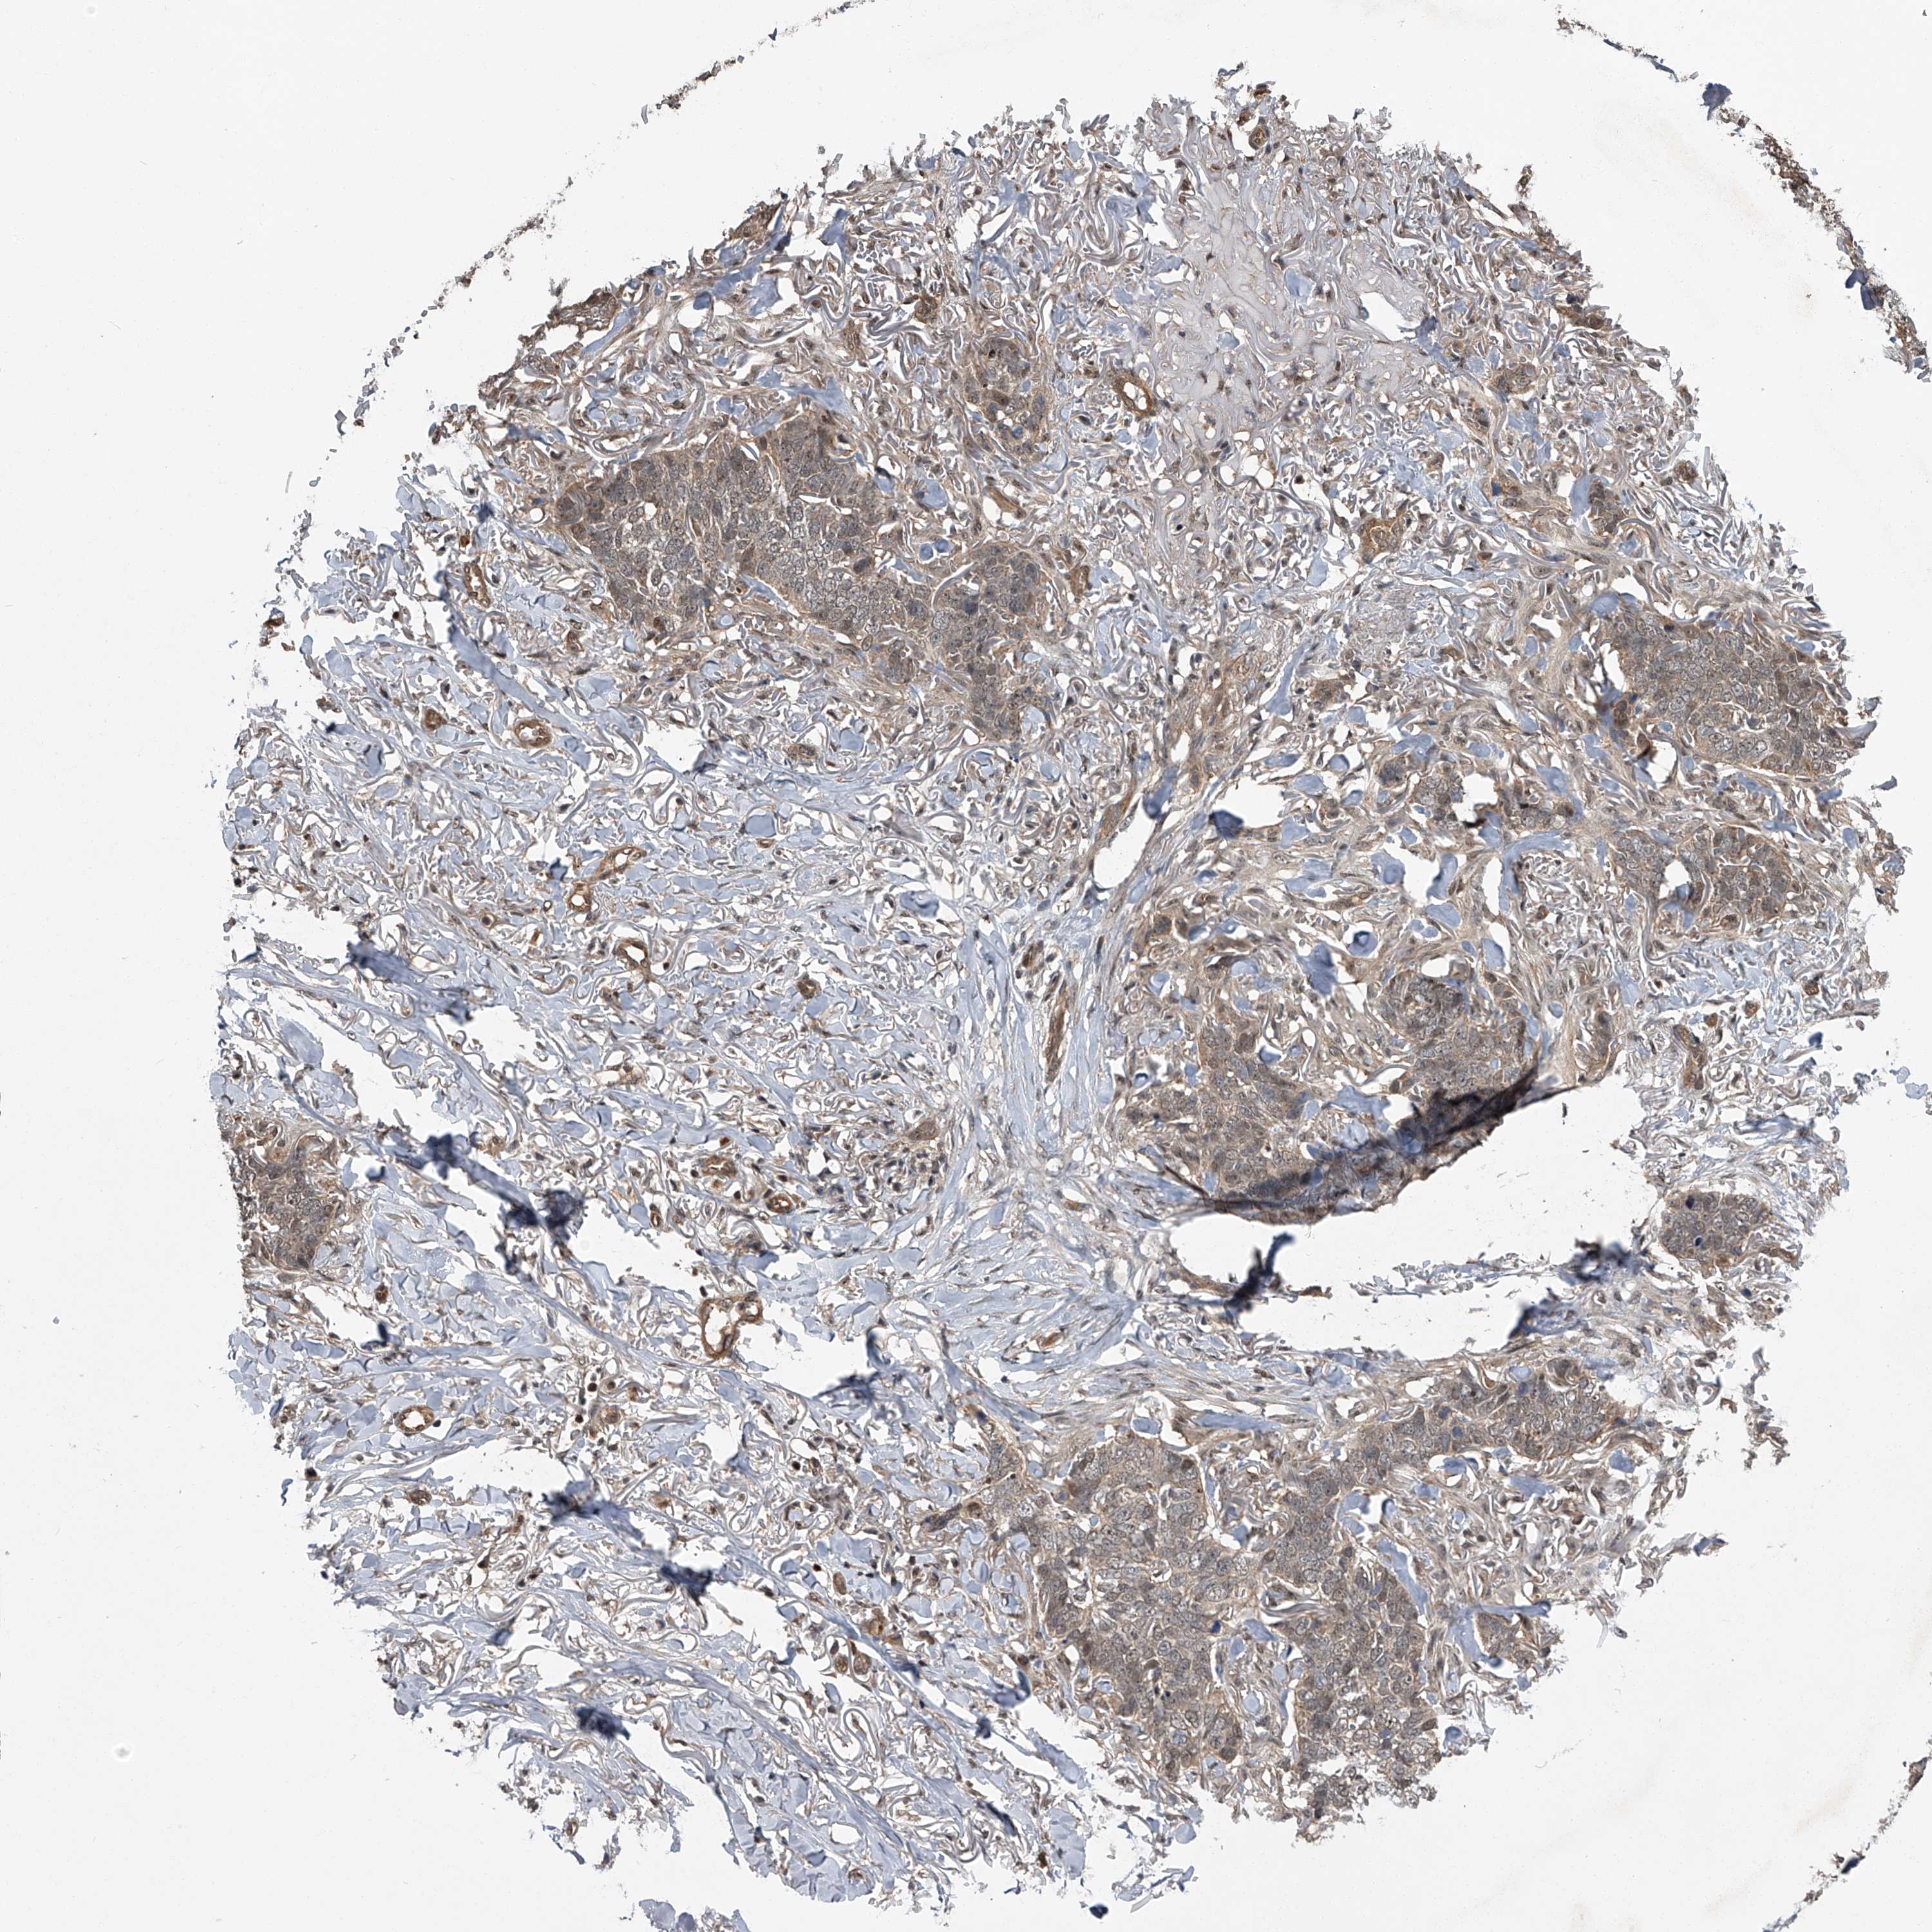

SKIN CANCER - Protein expressioni

A mouse-over function shows sample information and annotation data. Click on an image to view it in a full screen mode. Samples can be filtered based on level of antibody staining by selecting one or several of the following categories: high, medium, low and not detected. The assay and annotation is described here.

Antibody staining in the annotated cell types in the current human tissue is reported as not detected, low, medium, or high, based on conventional immunohistochemistry profiling in selected tissues. This score is based on the combination of the staining intensity and fraction of stained cells.

Each image is clickable and will lead to virtual microscopy that enables deeper exploration of all samples and also displays staining intensity scores, fraction scores and subcellular localization as well as patient and tissue information for each sample.

Antibody HPA031123

Staining

High

Medium

Low

Not detected

Intensity

Strong

Moderate

Weak

Negative

Quantity

>75%

75%-25%

<25%

None

Location

Nuclear

Cytoplasmic/membranous

Cytoplasmic/membranous,nuclear

Squamous cell carcinoma, metastatic, NOS